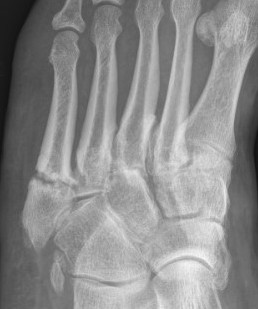

Zone 3 Fractures

Progression to nonunion of zone 3 fracture with nonoperative care